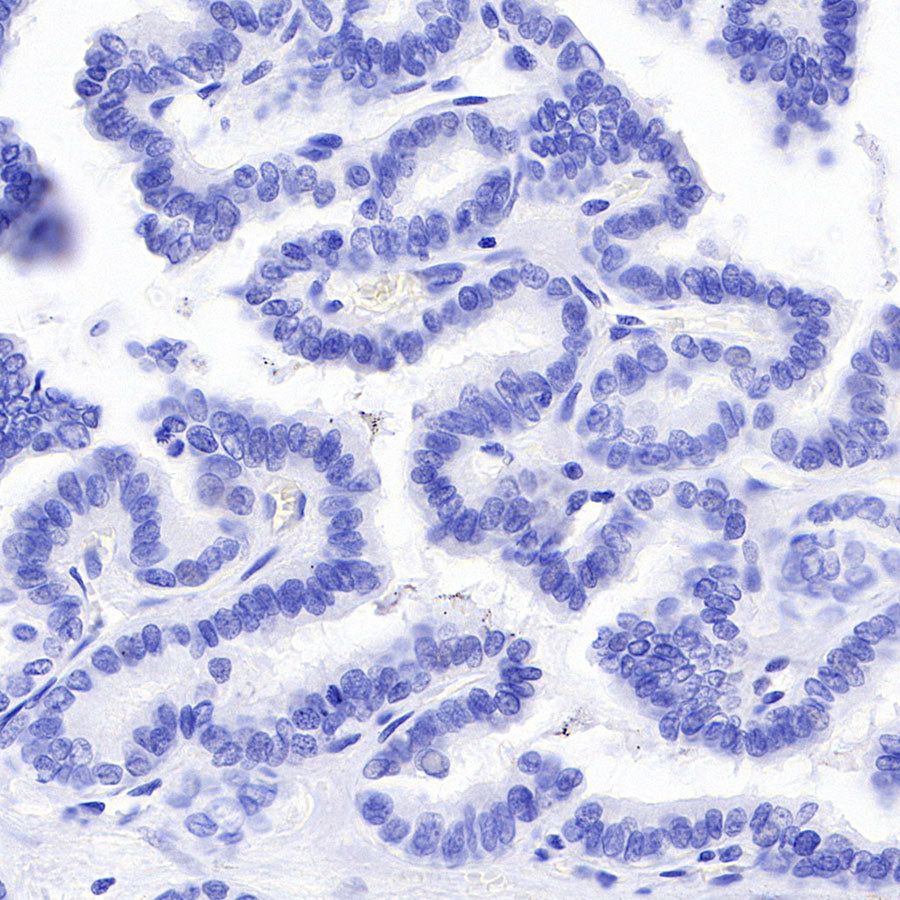

Negative control: IHC shows negative staining in paraffin-embedded human papillary thyroid carcinoma. Anti-Calcitonin antibody was used at 1/1000 dilution, followed by a HRP Polymer for Mouse & Rabbit IgG (ready to use). Counterstained with hematoxylin. Heat mediated antigen retrieval with Tris/EDTA buffer pH9.0 was performed before commencing with IHC staining protocol.

Negative control: IHC shows negative staining in paraffin-embedded human colon cancer. Anti-Calcitonin antibody was used at 1/1000 dilution, followed by a HRP Polymer for Mouse & Rabbit IgG (ready to use). Counterstained with hematoxylin. Heat mediated antigen retrieval with Tris/EDTA buffer pH9.0 was performed before commencing with IHC staining protocol.

Negative control: IHC shows negative staining in paraffin-embedded human pancreatic cancer. Anti-Calcitonin antibody was used at 1/1000 dilution, followed by a HRP Polymer for Mouse & Rabbit IgG (ready to use). Counterstained with hematoxylin. Heat mediated antigen retrieval with Tris/EDTA buffer pH9.0 was performed before commencing with IHC staining protocol.

Negative control: IHC shows negative staining in paraffin-embedded human cerebral cortex. Anti-Calcitonin antibody was used at 1/1000 dilution, followed by a HRP Polymer for Mouse & Rabbit IgG (ready to use). Counterstained with hematoxylin. Heat mediated antigen retrieval with Tris/EDTA buffer pH9.0 was performed before commencing with IHC staining protocol.

Negative control: IHC shows negative staining in paraffin-embedded human skeletal muscle. Anti-Calcitonin antibody was used at 1/1000 dilution, followed by a HRP Polymer for Mouse & Rabbit IgG (ready to use). Counterstained with hematoxylin. Heat mediated antigen retrieval with Tris/EDTA buffer pH9.0 was performed before commencing with IHC staining protocol.